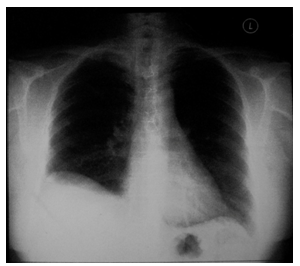

Figure 2 Post-operative chest X-ray.

CT scans of the shows a large intraparenchymal mass (size 10.7cm x 10.3cm x 8.5cm). This mass is benign in nature and thorax which pushes the trachea to the left. A connection is present between the mass and the right thyroid gland. There is associated collapse consolidation of the lateral segment of middle lobe of the lung Right thoracotomy and excision of the mass was performed. Intra-operatively, the mass is well-encapsulated, adjacent to the lung parenchyma and separated from the cervical thyroid gland. The mass received blood supply from the intrathoracic vessel. This mass was sent for histopathological examination.

Histopathological examination confirms that mass is composed of encapsulated nodular thyroid tissue medially and a large lipoma laterally. There was no evidence of malignancy.